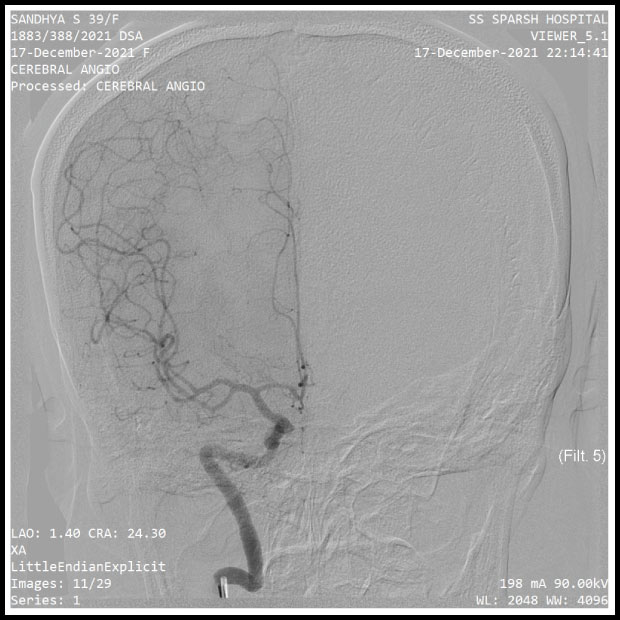

TEST REPORTS FROM THE HOSPITAL

Pics show the test reports from the hospital. The brain aneurysm is clearly noticeable.